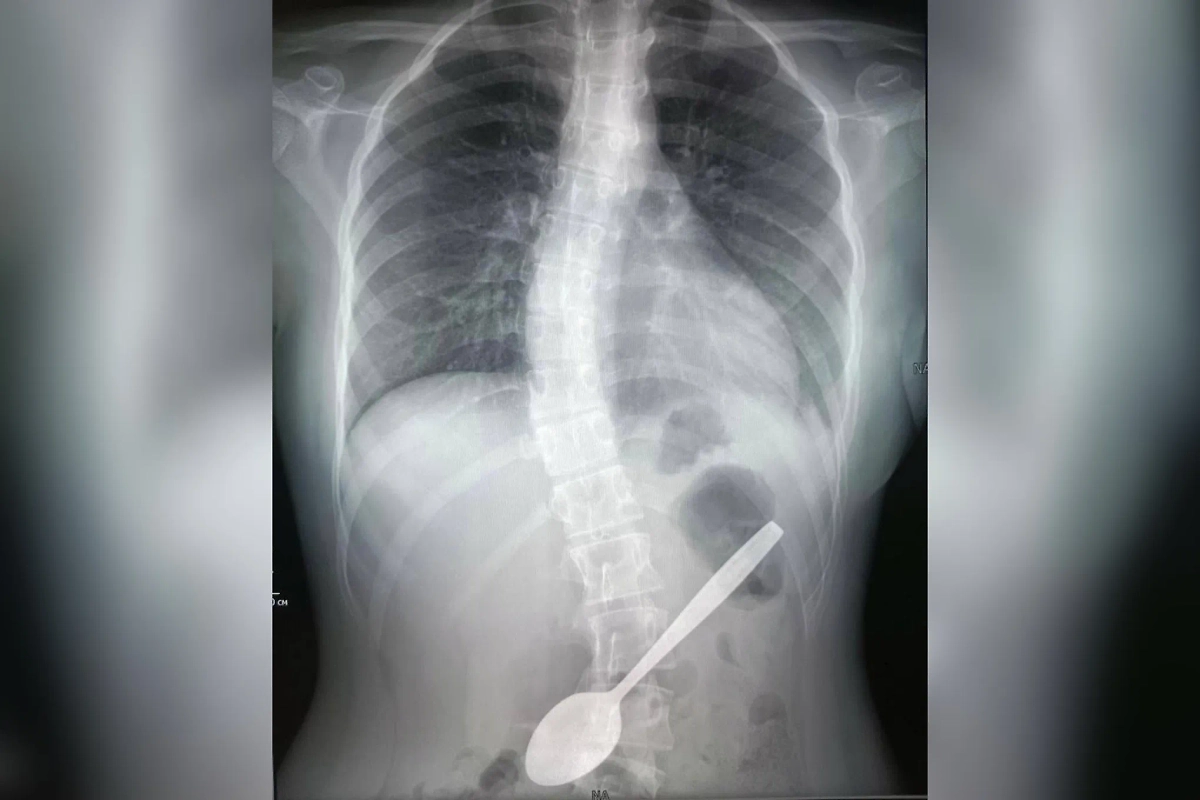

Врачи Центра Рошаля извлекли 15-сантиметровую ложку из желудка девочки. Фото © пресс-служба Министерства здравоохранения Московской области

Оперативно проведённая рентгенография подтвердила наличие инородного тела. Как выяснилось, ложка заняла опасное положение: один конец упирался в желудок, а другой — в двенадцатиперстную кишку.